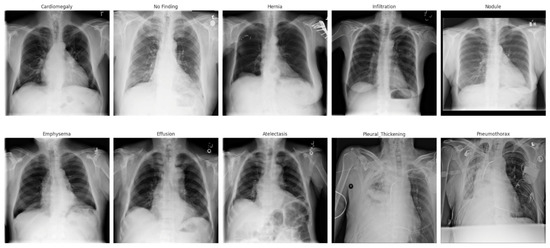

- Wang, X.; Peng, Y.; Lu, L.; Lu, Z.; Bagheri, M.; Summers, R.M. Chestx-ray8: Hospital-scale chest x-ray database and benchmarks on weakly-supervised classification and localization of common thorax diseases. In Proceedings of the IEEE Conference on Computer Vision and Pattern Recognition, Honolulu, HI, USA, 21–26 July 2017; pp. 2097–2106. [Google Scholar]